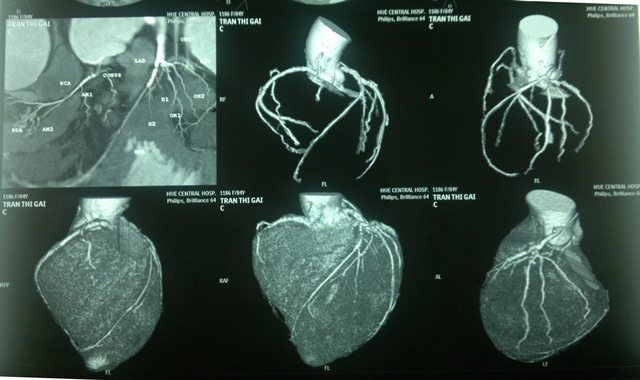

Chụp cắt lớp vi tính mạch vành

Đánh giá được hình ảnh động của mạch vành cũng như mức độ hẹp và vị trí hẹp. Tuy nhiên nếu mạch vành tim bị vôi hóa nhiều thì độ chính xác sẽ giảm.